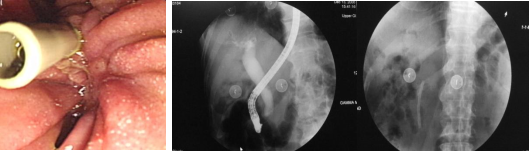

ERCP—小切口大作用,镜让治疗

更精准

近年来,消化内科通过不断提高技术水平和业务能力,内镜下治疗例数逐步增加,成功率稳步提升提高;内镜逆行胰胆管造影 (ERCP)技术目前已成为解决胆胰疾病的主要治疗方法,该技术已在我科成熟开展,为胆胰疾病患者提供了更加精准且微创的治疗方法,为隆阳区及周边地区胆胰疾病患者带来更多治疗选择。该治疗无需开放、手术恢复快,切口微小。